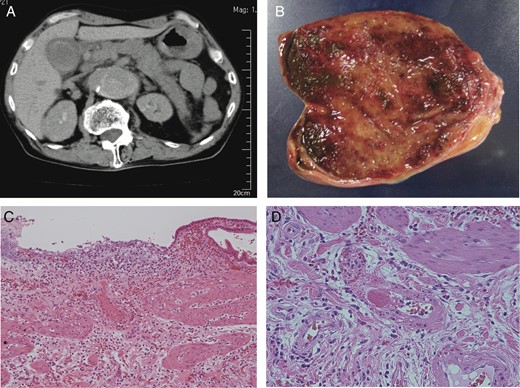

A 69-year-old male who had an 8-year history of Stanford type B aortic dissection presented with vomiting and abdominal pain. Physical examination revealed right upper abdominal tenderness, but no muscular defense. Blood tests revealed leukocytosis and elevated levels of amylase, but other laboratory data were within normal range. Abdominal sonography showed the inflammatory thickened gallbladder wall without any gallstones and biliary sludge. Contrast-enhanced computed tomography (CT) also showed the enlargement of the false lumen compared with a study 5 years earlier. The gallbladder and pancreatic body and tail were swollen, indicating acute pancreatitis and AAC (Fig. 1A). A highly enhancing lesion was detected in the gallbladder, which appeared to be the gallbladder hemorrhage. Laparotomy revealed necrotized cholecystitis with dominant histopathologic changes at the fundus of the gallbladder (Fig. 1B). Pathological exams showed partial mucosal defect and submucosal bleeding in the whole gallbladder wall (Fig. 1C). In addition, fresh thrombi formation was found in the arterioles at the fundus and less frequently in the body/neck of the gallbladder (Fig. 1D).

(A) CT showed Stanford type B aortic dissection, gallbladder wall thickness without gallstones and swollen pancreas. (B) Macroscopic examination showed the necrosis of the gallbladder fundus. (C) Histological examination revealed that partial mucosal defect, mucosal/submucosal arterial thrombi and submucosal bleeding in the body of the gallbladder wall (H&E ×100). (D) Histological examination revealed the fresh thrombi formation in the arterioles at the fundus of the gallbladder (H&E ×400).